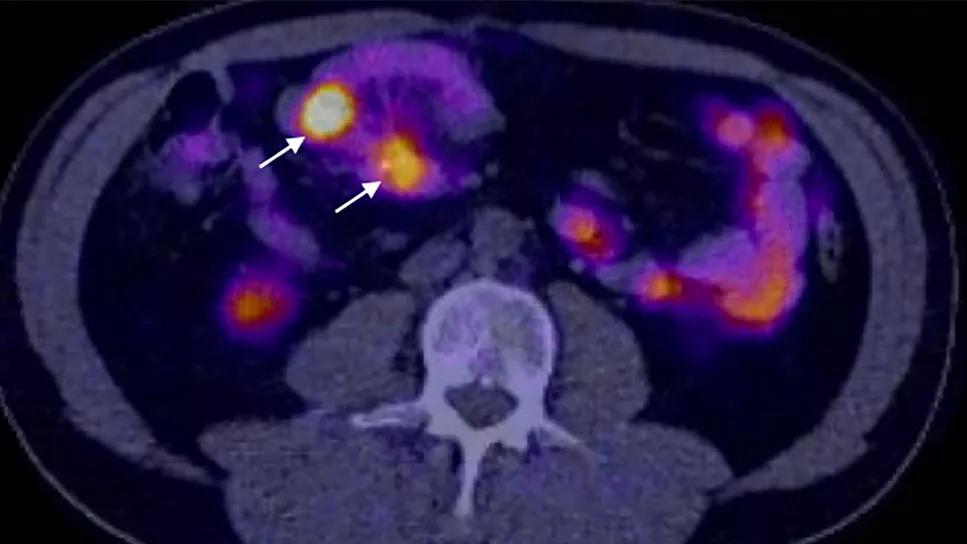

Dr. Berber’s team set out to compare this new method to existing imaging modalities such as DOTATATE PET scans. “When you look at these types of tumors through the infrared camera, it's almost like suddenly having night vision,” explains Dr. Berber. “They appear as bright dots.”

• 30% were seen in preoperative DOTATE PET scan.